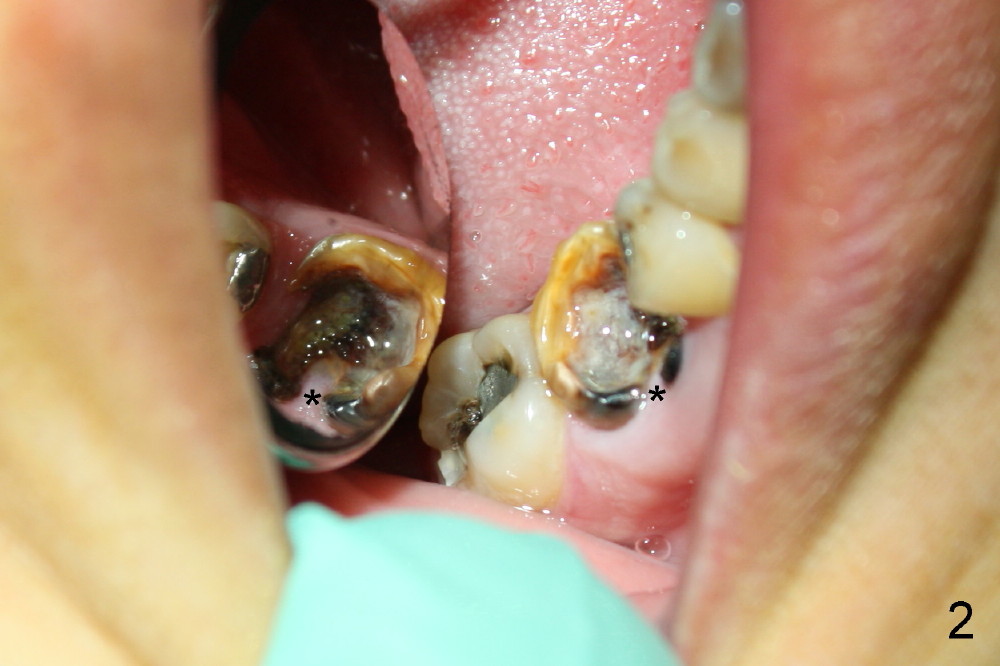

A 38-year-old lady agrees to have implant placement 7 years after loss of the crown of the lower right first molar (Fig.1,2). When the tooth is extracted, the septum is found to be low (Fig.3,4). To confirm it, a PA is taken (Fig.5). To initiate an osteotomy in the septum, it is trans-sectioned with thin osteotomes as shown in Fig.4 insert (black line). A 2 mm pilot drill is placed in the septum (Fig.6: P). The osteotomy is enlarged by 2.5-4.0 mm reamers (Fig.7,8), followed by insertion of 6x17 mm tapered tap at the depth 14 mm (Fig.9). The osteotomy is further enlarged by 4.5 and 5.0 mm reamers. A 6.0x14 mm one piece implant is placed initially. The trajectory is not ideal. A 6.0x14 mm one piece implant is placed initially. The trajectory is not ideal. The implant is removed from the osteotomy partially and reinserted with improved trajectory (Fig.11, compare to Fig.10 (red line)). Primary stability is high. There is not much bone mesiodistally so that the trajectory is easily changed in that direction. After abutment preparation, mixture of autogenous bone (harvested from reamers) and allograft is placed in the residual mesial and distal sockets (Fig.12). To contain the bone graft, an immediate provisional is placed (Fig.13 P). The occlusal plane of the provisional is significantly lower than that of the adjacent teeth to avoid micromovement of the implant. The patient is advised to eat soft food on the left side. Six days postop, the patient returns for prophy. The provisional is removed; the bone graft appears to be incorporating into the socket (Fig.14). After recementation, the provisional remains in place for 3.5 months; PA shows increased bone density in the mesial and distal sockets (Fig.15, compare to Fig.5,11). Due to insurance coverage, the patient defers fabrication of definitive restoration for at least 7 months. The immediate provisional is finally lost 8.5 months postop: the gingiva attaches to the 1-piece implant (Fig.16), while the density of the mesial socket increases (Fig.17 *) with formation of the cortex (lamina dura) coronally (v). Before the provisional (Fig.18 P) is removed for cementation of the definitive restoration, black shadow (*) is noted over the buccal gingiva. It is partially due to buccal placement (Fig.19) and partially due to buccal atrophy over a period of 10.5 months postop. How to prevent buccal placement? Positioning the first pilot drill in the septum buccolingually is a key. Eleven months post crown (Fig.20 C) cementation, the black shadow remains, but there is no tenderness. If the implant threads are immediately underneath the periosteum, there is tenderness.